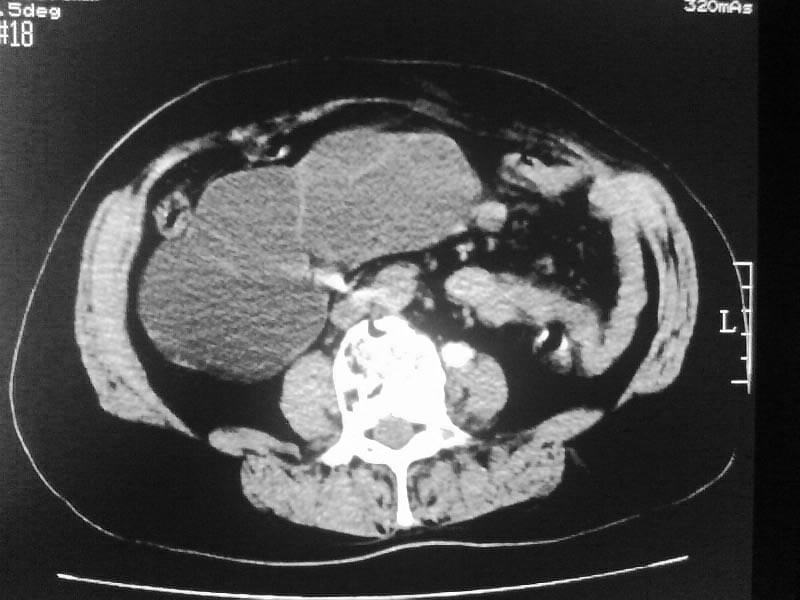

标题: CT20044:女,45岁,腰痛2年,双肾结石,右输尿管结石,右肾重度积 [打印本页]

标题: CT20044:女,45岁,腰痛2年,双肾结石,右输尿管结石,右肾重度积

支持双肾结石、右输尿管上端结石,右肾重度积水

右肾梗阻性积水。

双肾结石、双输尿管结石并右肾积水。

双肾,输尿管结石,右肾重度积水。